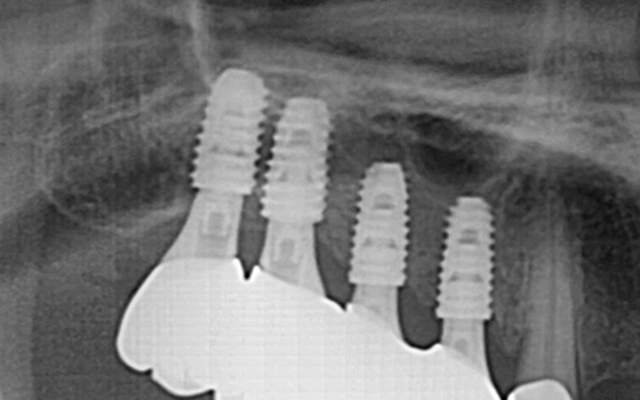

교합거상 케이스

- 마모·손상으로 낮아진 물림 높이를 정밀 분석 후 단계적으로 회복

- 턱관절·저작근 균형을 고려하여 기능과 심미를 동시에 개선